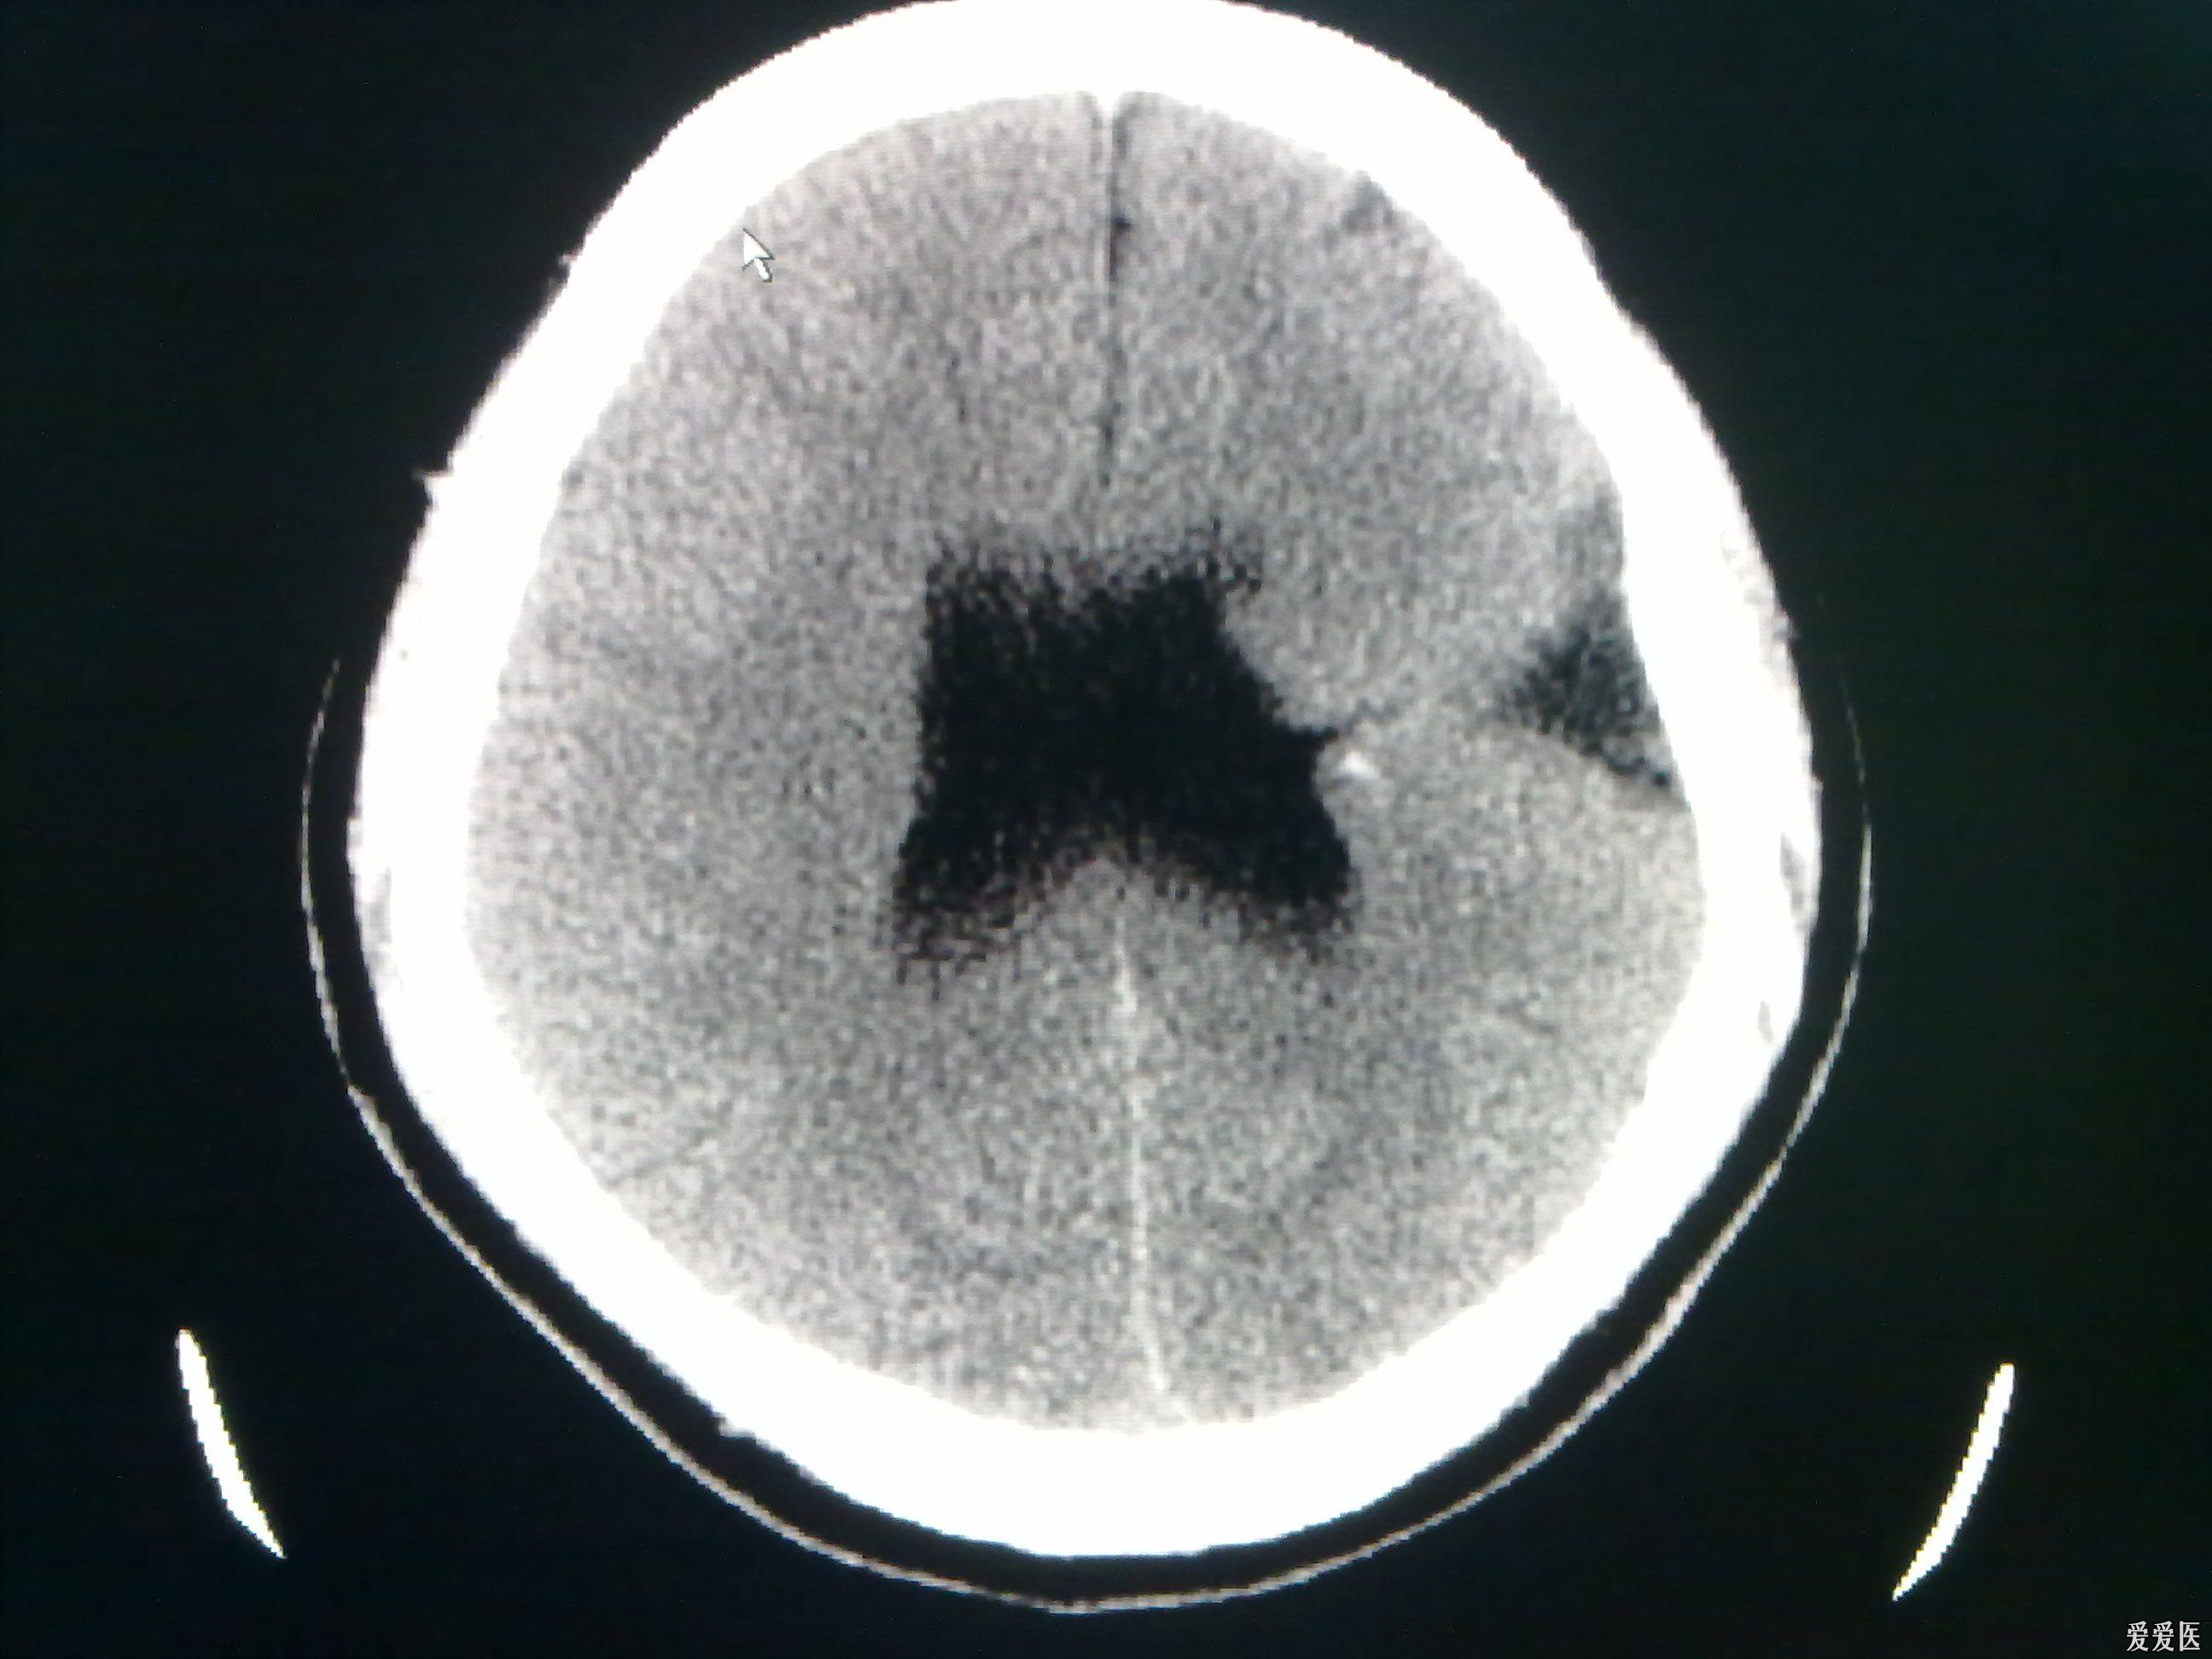

今天做到的病例脑裂畸形

图片尺寸2592x1944

今天做到的病例脑裂畸形

图片尺寸2592x1944

今天做到的病例脑裂畸形

图片尺寸2592x1944

今天做到的病例脑裂畸形

图片尺寸2592x1944